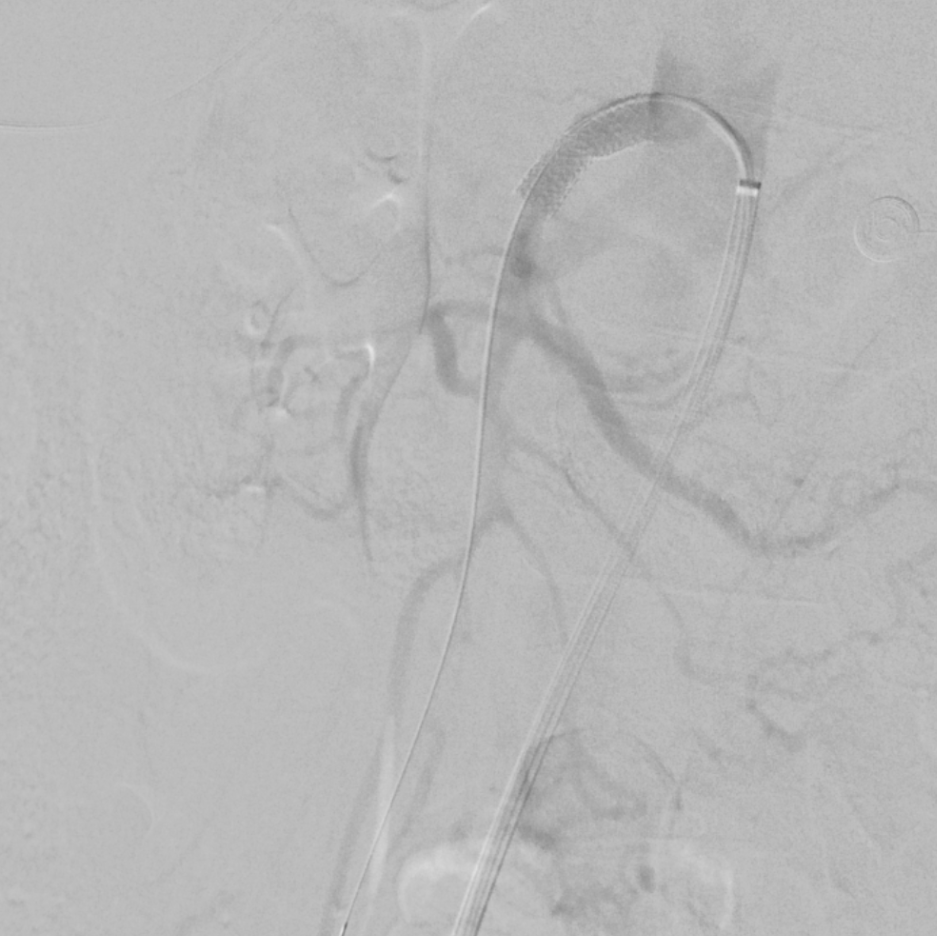

手术室内,介入外科、介入诊疗中心团队迅速就位。在局部麻醉下,介入外科团队精准穿刺股动脉,DSA造影清晰显示了夹层破口位置,随着支架的精准植入,复查造影显示:肠系膜上动脉主干通畅,各分支动脉显影良好,被阻断的肠道血供得以恢复!患者腹痛随即明显缓解。从入院到血管再通,全程仅用4个多小时,成功守住了肠道耐受缺血的“黄金救治窗”。